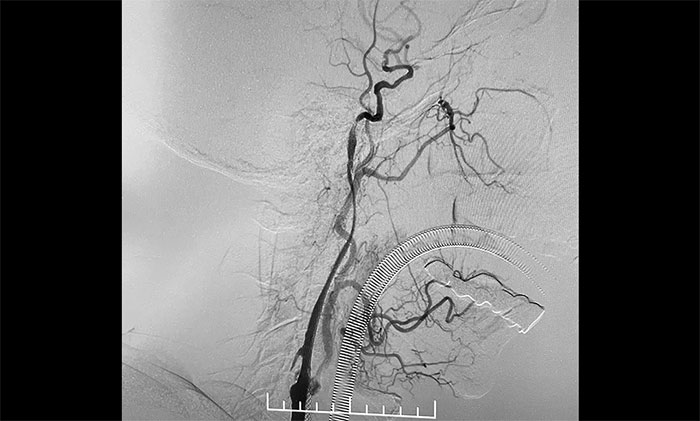

术中,超滑导丝、多功能导管经过反复尝试顺利通过左颈内动脉起始段,到达左颈内动脉远端显影段,路图见远端血管通畅,左大脑中动脉显影;随后,微导丝经多功能导管置于左颈内动脉海绵窦段,经微导丝送入保护伞至左颈内动脉岩骨垂直段并释放,再沿保护伞微导丝送入4x30mm球囊于左颈内动脉起始段,给予球囊扩张,撤除球囊后造影见左颈内动脉起始段再通,左颈内动脉、左大脑中动脉显影;最后,送入9x50mm支架,释放于左颈内动脉颈段至左颈总动脉末段,造影见左颈内动脉起始段显影明显改善,左颈内动脉、左大脑中动脉、左大脑前动脉显影可,行3D造影见左颈内动脉颈段显影改善。行支架CT见支架成形可,行XperCT未见颅内出血。

▲ 左侧颈内动脉闭塞顺利开通

手术圆满完成,席刚明教授团队、麻醉科团队及导管室团队通力合作,耐心、仔细地克服了手术的所有难点。左颈内动脉从“无”到“有”,正所谓“精诚所至,金石为开”,顺利为患者解除危机。